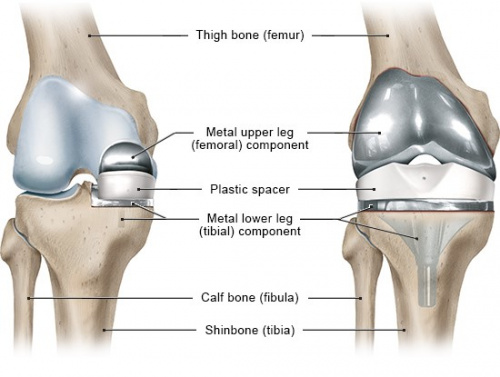

تعویض مفصل زانو برای آرتروز زانو چیست؟

آرتروپلاستی زانو نوعی جراحی ارتوپدی هست که با استفاده از آن سطوح مفصلی استخوان ران و درشت نی ساق در مفصل زانو با سطوح مصنوعی جایگزین می گردد. این جراحی معمولا برای آرتروز زانو و روماتیسم زانو و انحراف امتداد زانو انجام می شود. تعویض مفصل زانو به دو روش کامل( TKR یا TKA ) و نیمه کامل (UKA یا PKR) انجام می گیرد.

برای تعویض مفصل زانو شدت درد و ناتوانی بیمار عامل تعیین کننده جهت تصمیم جراحی می باشد. اگرچه عملا سن و وزن هم برای تصمیم جراحی و نوع جراحی مد نظر قرار می گیرند.

تعویض مفصل زانو معمولا موجب بهبود درد زانو و کیفیت زندگی بیماران می شود.

عمر مفصل های مصنوعی زانو بین 10 تا 20 سال هست.

تعویض نیمه کامل مفصل زانو (PKR یا UKA)

تعویض نیمه کامل مفصل زانو جراحی برای استئوآرتریت زانو هنگامی که قسمتی از زانو درگیر باشد مورد استفاده قرا می گیرد و در آن قسمت های آسیب دیده مفصل زانو تعویض می شود.

PKR مفصل زانو در حال حاضر به یک درمان پذیرفته شده برای بیماران مسن تر با آرتروز قسمت داخلی زانو تبدیل شده است.

بطور کلی در تعویض نیمه کامل مفصل زانو، درد بعد از عمل بیمار کمتر بوده و دوره بهبودی کوتاهتری نسبت به روش تعویض کامل زانو دارد، علاوه بر این، برش جراحی کوچکترو آسیب بافت کمتر هست.

برای این روش زانوی بیمار نباید ناپایدار باشد و یا محدودیت شدید در خم و راست شدن داشته باشد.

تعویض کامل زانو ( TKR یا TKA )

تعویض کامل زانو، با سابقه ربع قرن، به طور کلی برای بسیاری از بیماران تسکین درد خوبی فراهم می کند. حرکت و عملکرد بیماران نیز بهبود می یابد.